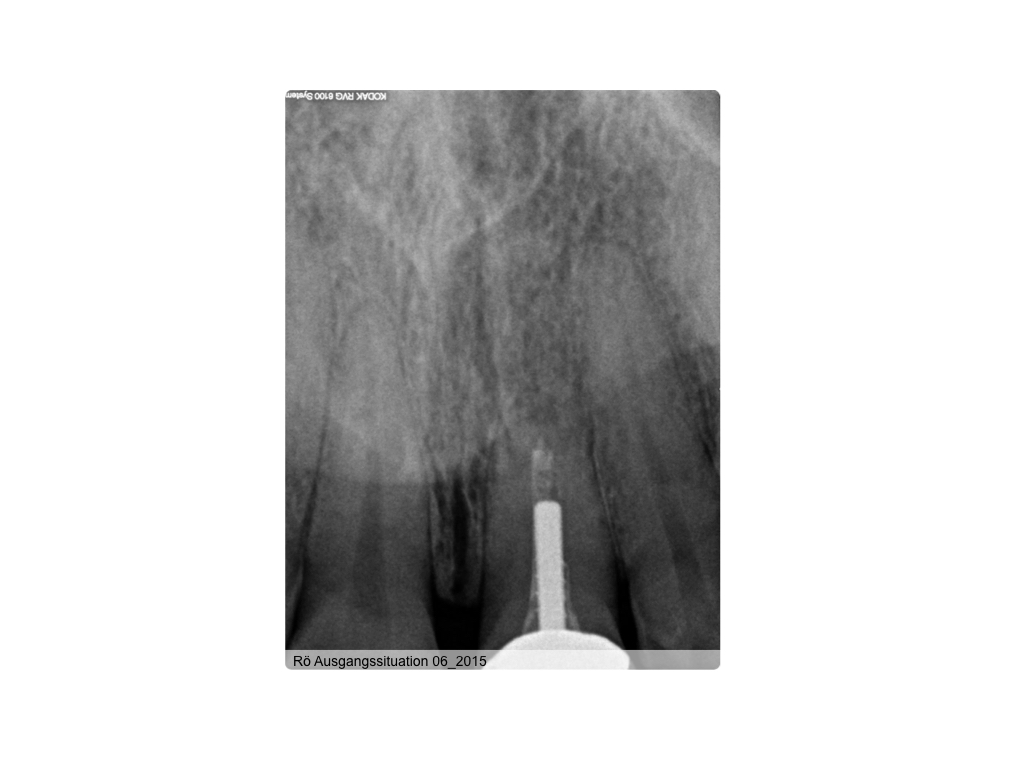

WS 04082016.001 Veröffentlicht 2. August 2016 am 1024 × 768 in Zustand nach traumatischer Zahnverletzung mit nachfolgender Wurzelbehandlung und Wurzelspitzenresektion